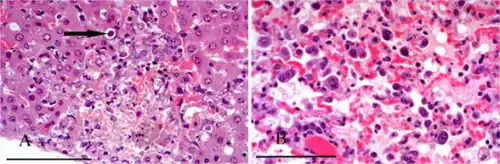

![]() | |

| False-color electron micrograph of a Plasmodium sporozoite | |